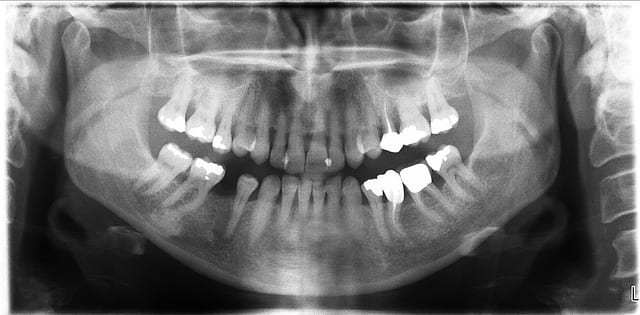

patiente 62 ans région Parisienne, appelle pour un avis, son praticien, paro, imlpanto etc... lui dit que sa paro n'a plus besoin de soin et propose pour les 6 antérieurs (j'ai le devis sous les yeux) 6 Inlay Core et 6 CCM...

Les panos sont du départ, les photos sont après un nettoyage ...profond et soins.

le problème de départ de cette patiente est paro...et bien sur l'ortho est une bonne idée, mais je ne pense pas que l'ortho permette de rétablir une DV correcte.

donc dans un premier temps détartrage, détartrage, détartrage Wax up, ....surfaçage couronne , amalgame à la benne taille des postérieurs inférieure et pose de provisoires pour valider la nouvelle DV.

à l'examen des coupes pano, franchement je ne crois pas que ce soit le bon choix.